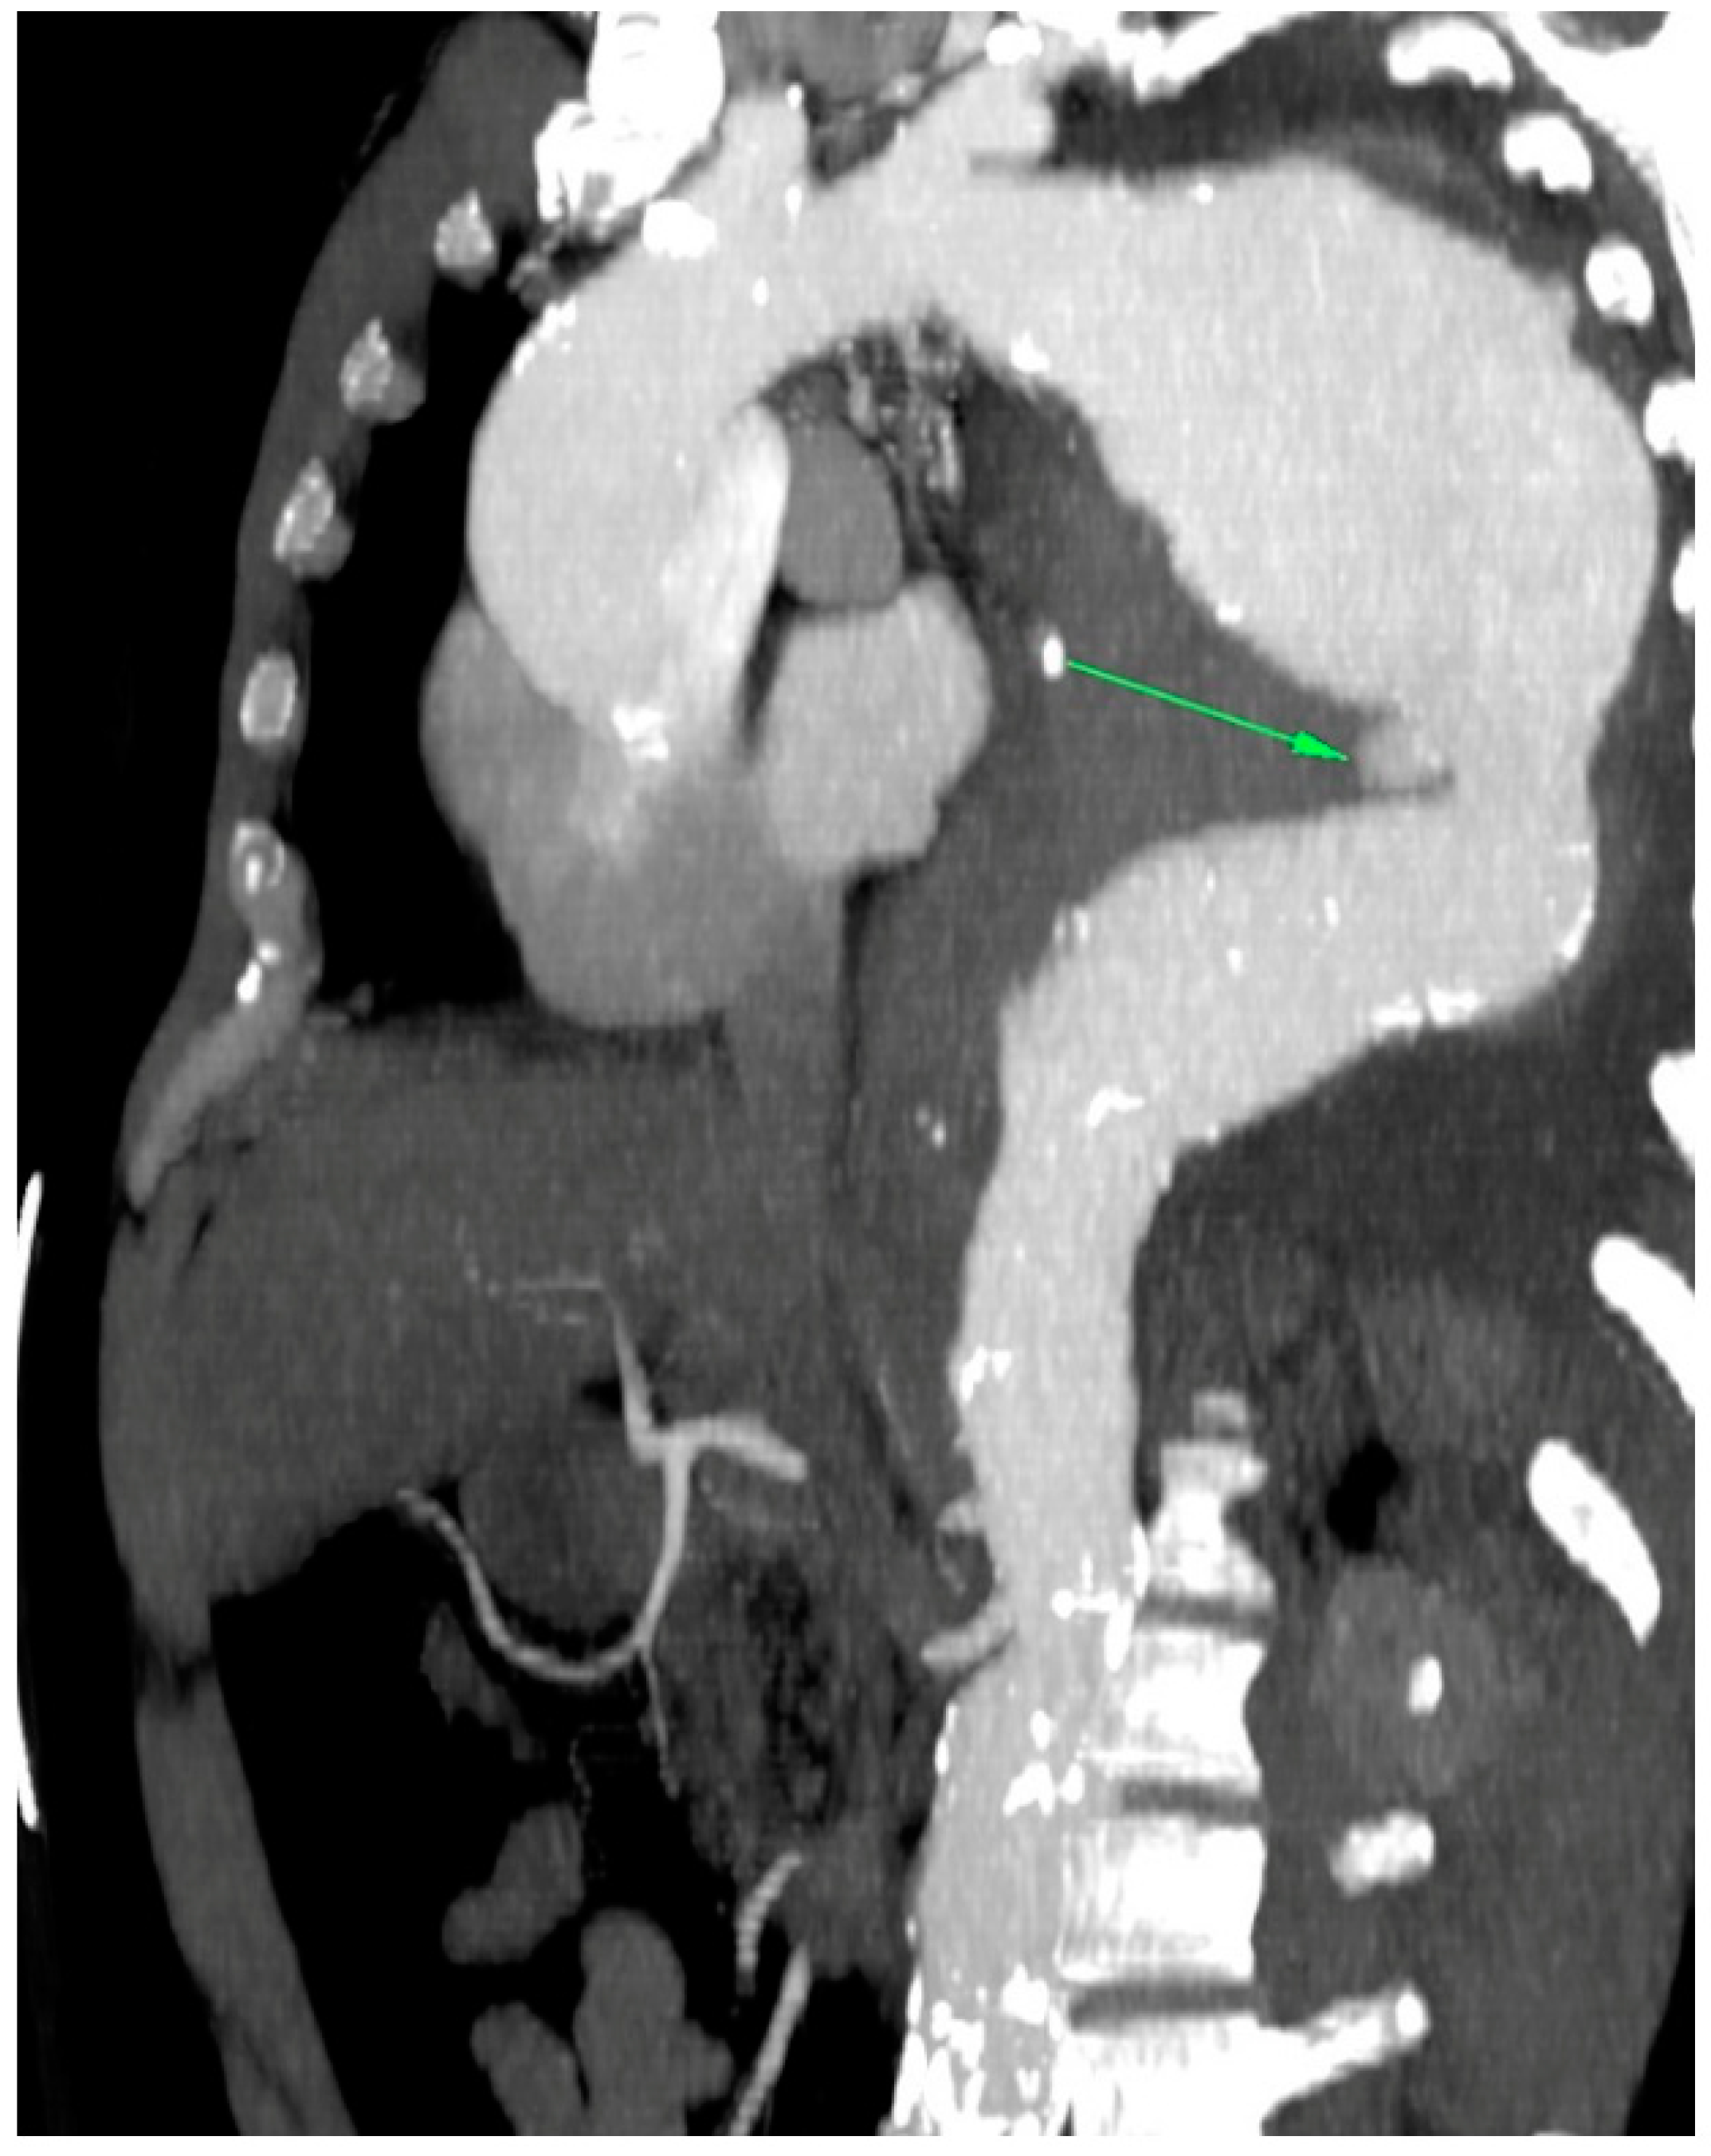

In the primary aortic group, 64% had an aneurysm (Figure 1), 18% had an aortic dissection, and 18% a PAU. In the secondary aortic group, 17% had an iatrogenic aortic lesion after spine surgery, 58% a trauma, and 25% an aortoesophageal fistula (Figure 2 and Figure 3). All patients underwent CT scan for diagnosis and after the surgery (Figure 4). Percutaneous access was performed in 31.8% of the patients in the primary aortic and 41.7% in the secondary aortic group (p = 0.566). An operation in local anesthesia was performed in 31.8% of the patients in the primary aortic group and 25% in the secondary aortic group (p = 0.677). Median duration of hospital stay was longer in the primary aortic group compared to the secondary aortic group (14.5 vs. 8 days, p = 0.746). Simultaneous surgery was similarly frequent in both groups (22.7% vs. 25%, p = 0.881). Procedures included: hepatic artery bypass, aortic arch debranching, surgical treatment of a pelvic fracture, thoracotomy, bowel resection, trepanation, ECMO implantation, and splenectomy.

Figure 2.

CT-scan of a thoracic aortic aneurysm rupture with an aortoesophageal fistula (green arrow).

In the patients included in our analysis, there were three patients treated for an aortoesophageal fistula. Only one patient, treated for primary fistula with esophagectomy and TEVAR in the same procedure, survived (Figure 2, Figure 3, Figure 4 and Figure 5). This patient is still alive and in follow-up. The other two patients treated for a secondary fistula due to anastomotic leak after esophagectomy for esophageal cancer died after TEVAR. The incidence of an aortoesophageal fistula after TEVAR for primary aortic pathologies is low, as demonstrated in the European Registry of Endovascular Aortic Repair Complications (1.5%). In this cohort, the highest 1-year survival (46%) could be achieved via an aggressive treatment, including radical esophagectomy and aortic graft replacement [41]. In our patient population, we did not treat patients with a secondary fistula after TEVAR. In a 2014 review, 55 articles were included which reported on 72 patients treated with TEVAR for aortoesophageal fistula. Similar to our data (100% technical success rate), the technical success rate was 87.3%. Nevertheless, the overall 30-day mortality was significantly lower (19.4%) than in our series [42]. In a 2009 meta-analysis, 43 patients with aortoesophageal fistula were identified. Mortality after TEVAR was 19%. Patients who underwent esophageal surgery in the first month after TEVAR had lower fistula-related mortality during 6 months of follow-up compared to the other patients (p = 0.018) [43].